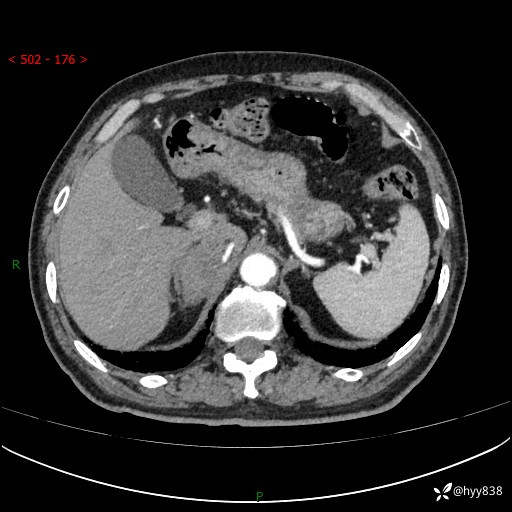

【患者信息】:76岁/男

【主诉】:检查发现右侧肾上腺占位6天

【现病史及既往史】:患者6天前体检发现右侧肾上腺占位,无腰痛,无放射痛,无尿频、尿急、尿痛及肉眼血尿,无畏寒、发热,无恶心、呕吐,今为求进一步治疗,遂来我院就诊,门诊拟“右侧肾上腺占位”收住入院。 起病以来,患者精神、饮食、睡眠可,大小便如常,体力体重无明显变化。

【检查】:肾上腺CT平扫+增强